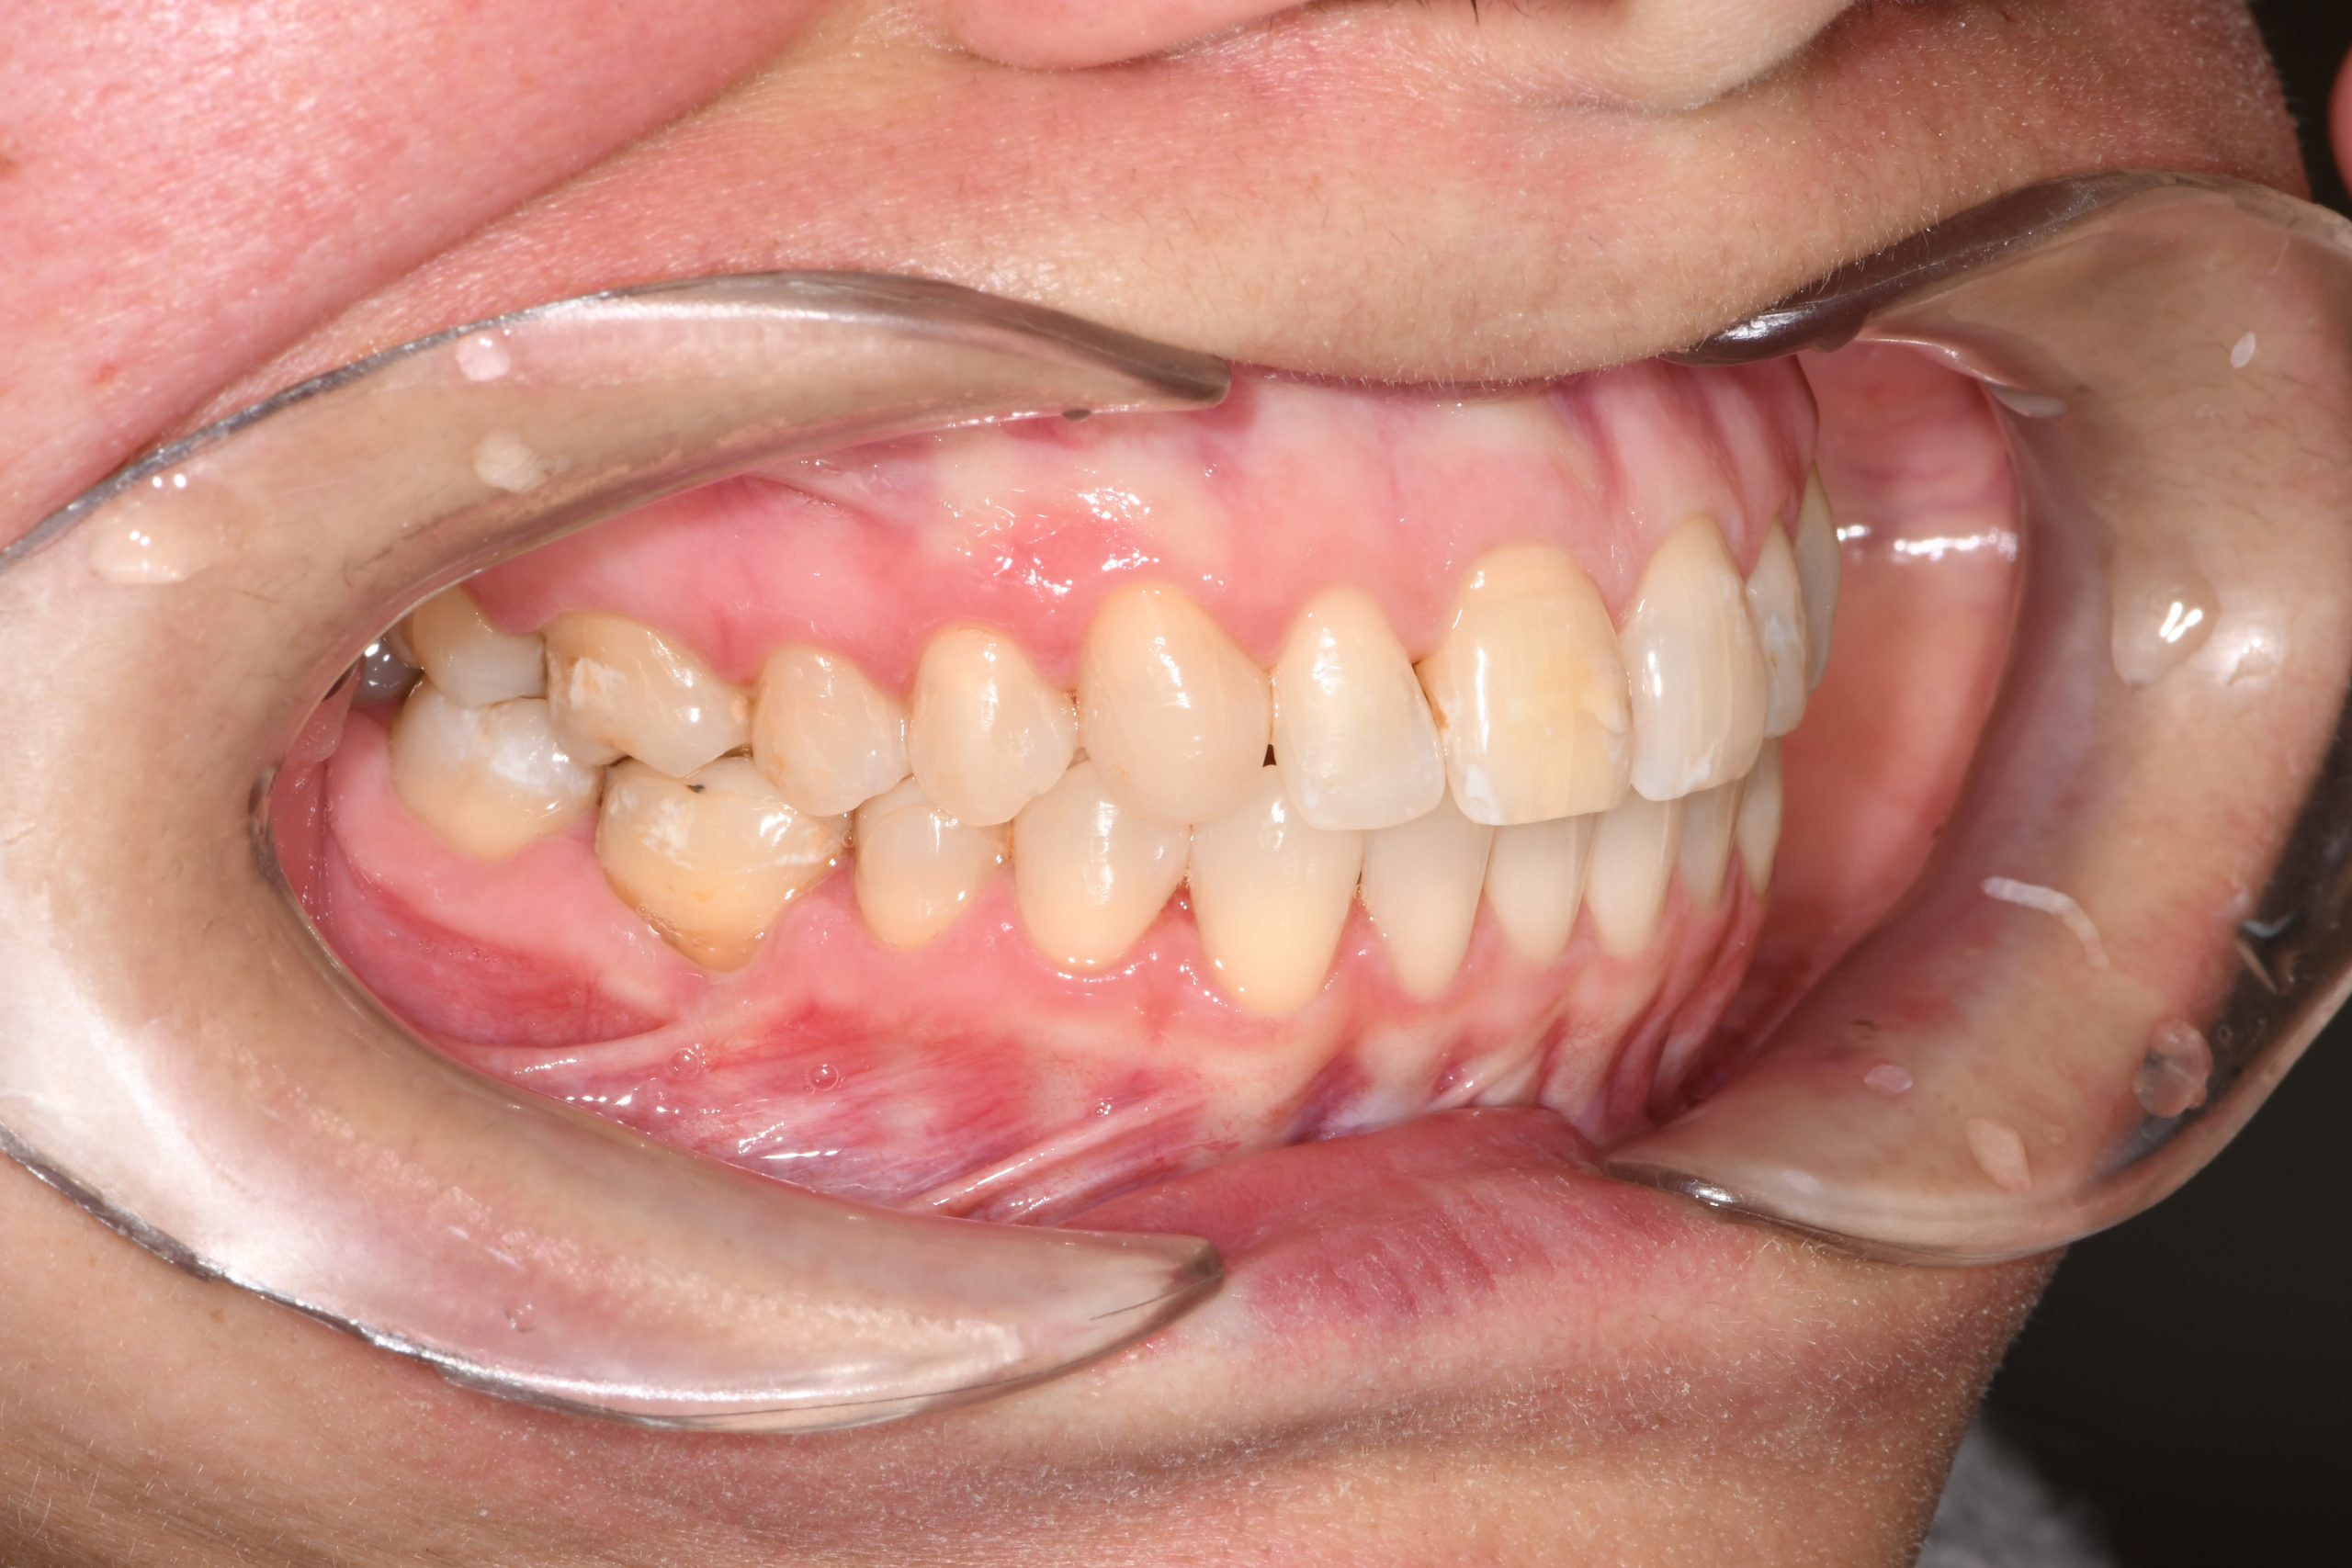

Az elmúlt évekből rengeteg szakmai referenciát tudnánk bemutatni, amelyek különböző fogszabályozási problémákat oldottak meg. Válogatva a több száz esetből, ezen az oldalon olyan képeket, információkat igyekeztünk bemutatni, amelyeknek a segítségével a jövőbeni pácienseinknek azt tudjuk üzenni: A Te fogsorod is lehet gyönyörű!

(Képeket a Pácienseink külön írásos beleegyezésével mutatjuk be!)